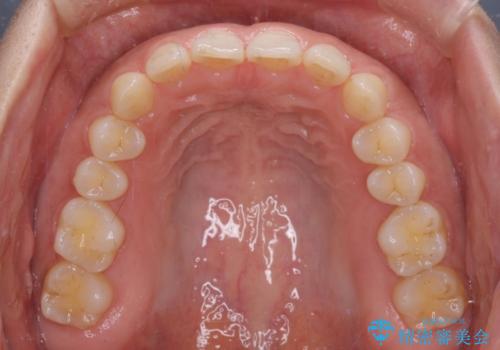

【モニター】ディープバイトを治す ワイヤー装置による矯正治療

- 顎が疲れるほどのディープバイトを気にして来院された患者様です。

手前に傾斜している奥歯を直立させながら、歯列全体の平面を均一に整えることでディープバイトを改善していくこととしました。

ディープバイトは咬合力が強いことが特徴であり、より良い仕上がりとするために、臼歯部のコントロールを行いやすいワイヤー装置を用いて矯正治療を行うこととしました。

ディープバイトが改善されたことで、食いしばりしかできなかった状態からスムーズな歯ぎしりができるようになりました。